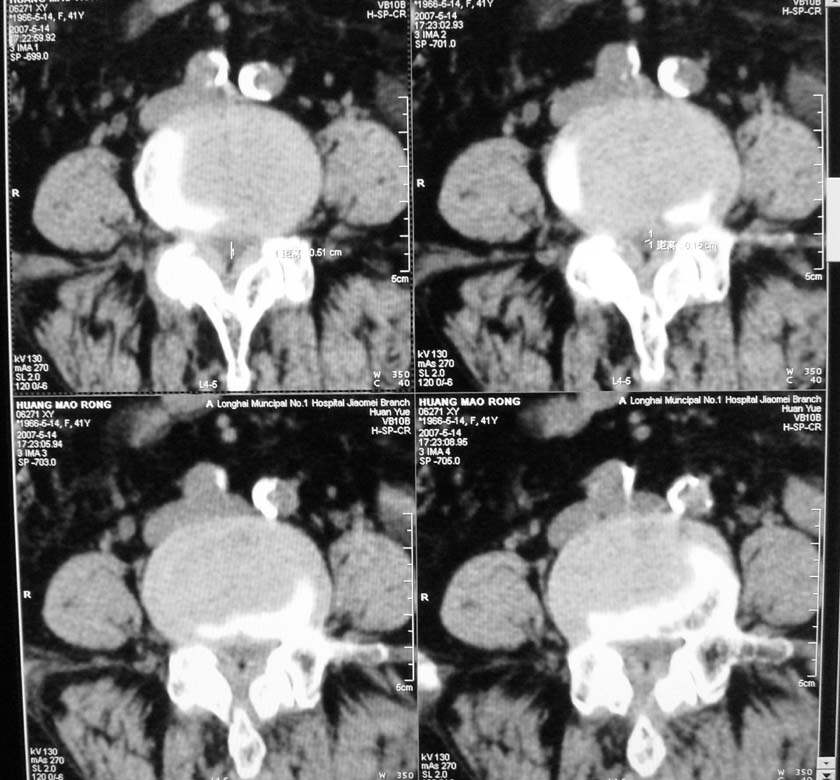

以下是引用jiangjing在2007-5-16 11:05:00的发言:[br]zhichi [br]ct所见:[br]l4-5椎间盘膨出,双侧黄韧带增厚,致使对应椎管变窄,硬膜囊受压.[br][br]l5-s1椎间盘后突,其后硬膜囊受压.l3-4椎间盘未见突出征象.[br]诸椎体边缘及对应椎小关节突骨质增生.腰椎生理曲度正常.[br]腹主动脉壁广泛钙化.[br]印象:[br]1、l4-5椎间盘膨出并双侧黄韧带肥厚及椎管狭窄。[br]2、l5-s1椎间盘突出。[br]3、腰椎及椎小关节退变。